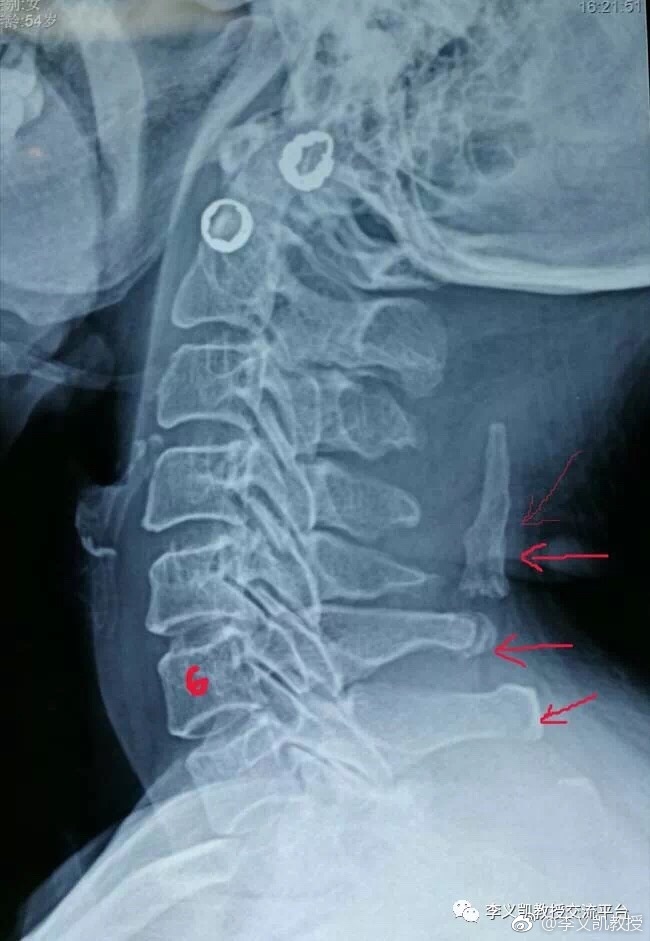

项韧带钙化X线片

项韧带长时间重复、单调、机械的动作或长期低头工作,使项韧带受到牵拉,造成慢性韧带劳损,日久钙盐沉积而形成韧带钙化或骨化。

青壮年时期,颈部曾有急性外伤,造成项韧带受伤,断裂,局部出血,渗出,肿胀,以后逐渐吸收,形成粘连纤维结节等改变,随着时间的延长钙盐逐渐沉积,发生钙化或骨化。